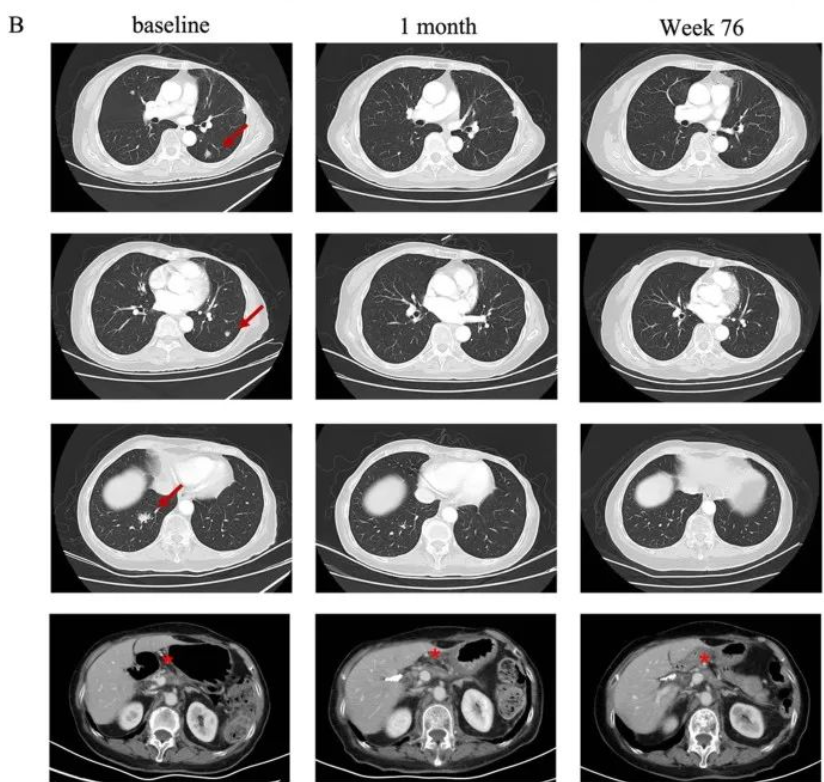

无癌生存已超8年!国研CAR-T疗法让肝癌患者重获新生!

一名50岁男性乙型肝炎肝硬化患者,2014年12月根据中国肝癌分期(CNLC)诊断为Ib期肝细胞癌,换着肝功能分级为Child-Pugh A诊断时,经过两次经导管动脉化疗栓塞术(TACE)获得部分缓解(PR)后,患者于2015年3月接受微波消融术(MWA)作为根治性治疗。但因病情发展迅速,于术后6周内出现IVCTT。考虑到经济原因,患者拒绝全身治疗,自愿参加CAR-T临床试验,并随后接受肝脏病变MWA抢救治疗和IVCTT伽马刀放射外科治疗。

令人欣喜的是,患者的甲胎蛋白在第14天从1210ng/mL迅速将至121ng/mL,并在接下来的两个月内逐渐恢复到正常范围,给予靶向GPC3的CAR-T细胞治疗后没有观察到肿瘤复发,迄今无瘤生存已超过8年(2015.07-2023.08)。

典型病例

总生存期超7年!国研CAR-T疗法给肝癌患者新的生存希望!

一名54岁男性乙型肝炎肝硬化患者,根据CNLC诊断为1b期HCC,并于2014年12月接受肿瘤切除手术。后来肝内肿瘤复发,反复多次进行TACE和微波消融后仍无法控制肿瘤进展,通过局部治疗(微波消融和伽马刀)控制肝内肿瘤、下腔静脉癌栓剂腹膜淋巴结转移瘤,经过CAR-T治疗后,患者于2016年7月已是无癌状态。

值得一提的是,该患者在没有任何进一步抗癌治疗的情况下保持无癌状态超5年,总生存时间超过7年(2016.07-2023.08)。